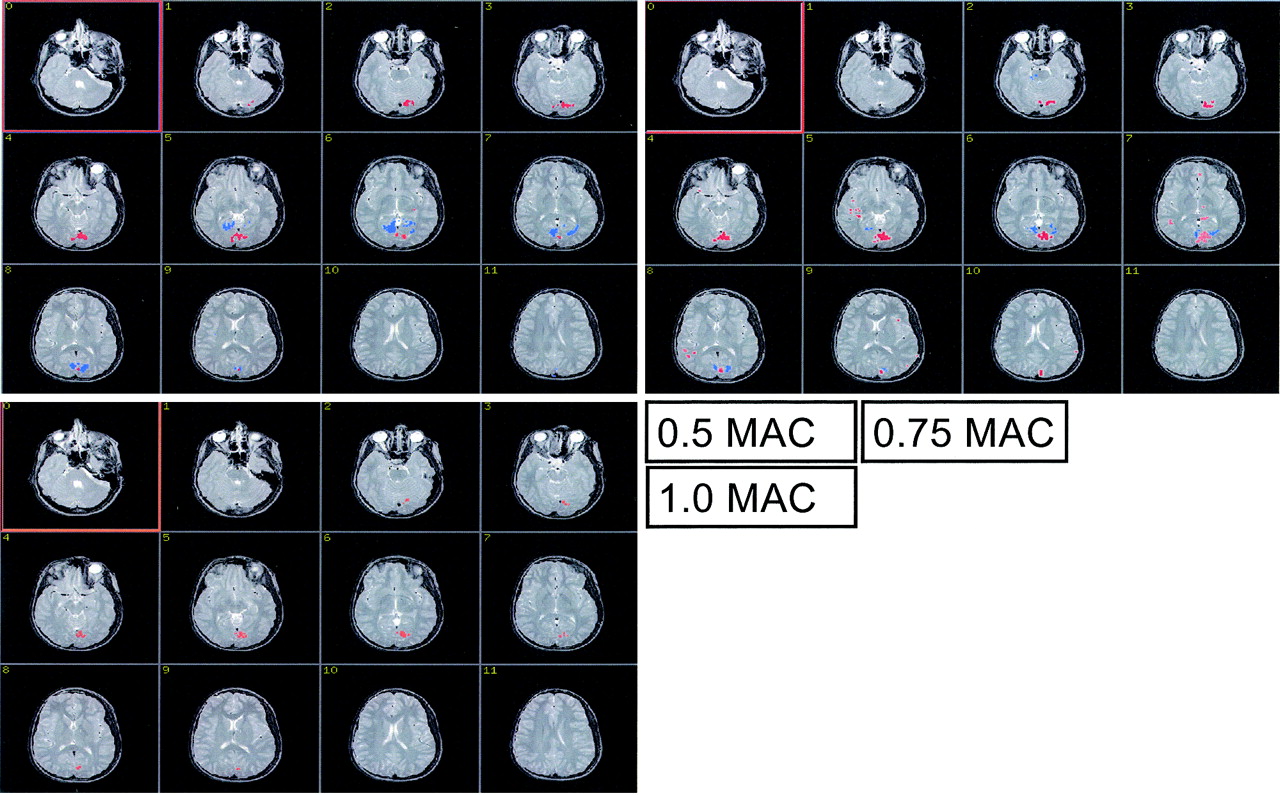

Figs 1A–C show the BOLD activation at the 3 levels of sevoflurane concentration in a single, representative subject. The positive (red) and the negative (blue) BOLD responses were spatially separated. The mean number of voxels with a positive or a negative BOLD signal intensity are shown in Figs 2A and 2B, respectively. The level of sevoflurane had a significant effect on the extent of activation of the positive BOLD response (FWilks = 4.572; df = 2 ,14; P = .03; ETA2 = 0.395). The data exhibited a significant quadratic trend (F = 8.040; df = 1; P = .013; ETA2 = 0.349). At 1.0 MAC we found activated voxels with a negative BOLD response in 3 subjects only. The extent of activation of the negative BOLD response failed to reach significance, though reduction between 0.5 MAC and 0.75 MAC was significant (F = 5.727; df = 15; P = .03; ETA2 = 0.276) and the data across all 3 concentration levels exhibited a significant linear trend (F = 7.033; df = 1; P = .018; ETA2 = 0.319).

The figure shows the cortical site of the positive BOLD response (red) and the negative BOLD response (blue) in a single child at the 3 levels of sevoflurane anesthesia. The extent of activation of the positive BOLD response is clearly largest, at 0.75 MAC. The extent of activation of the negative BOLD response can be seen to decline with increasing sevoflurane level.